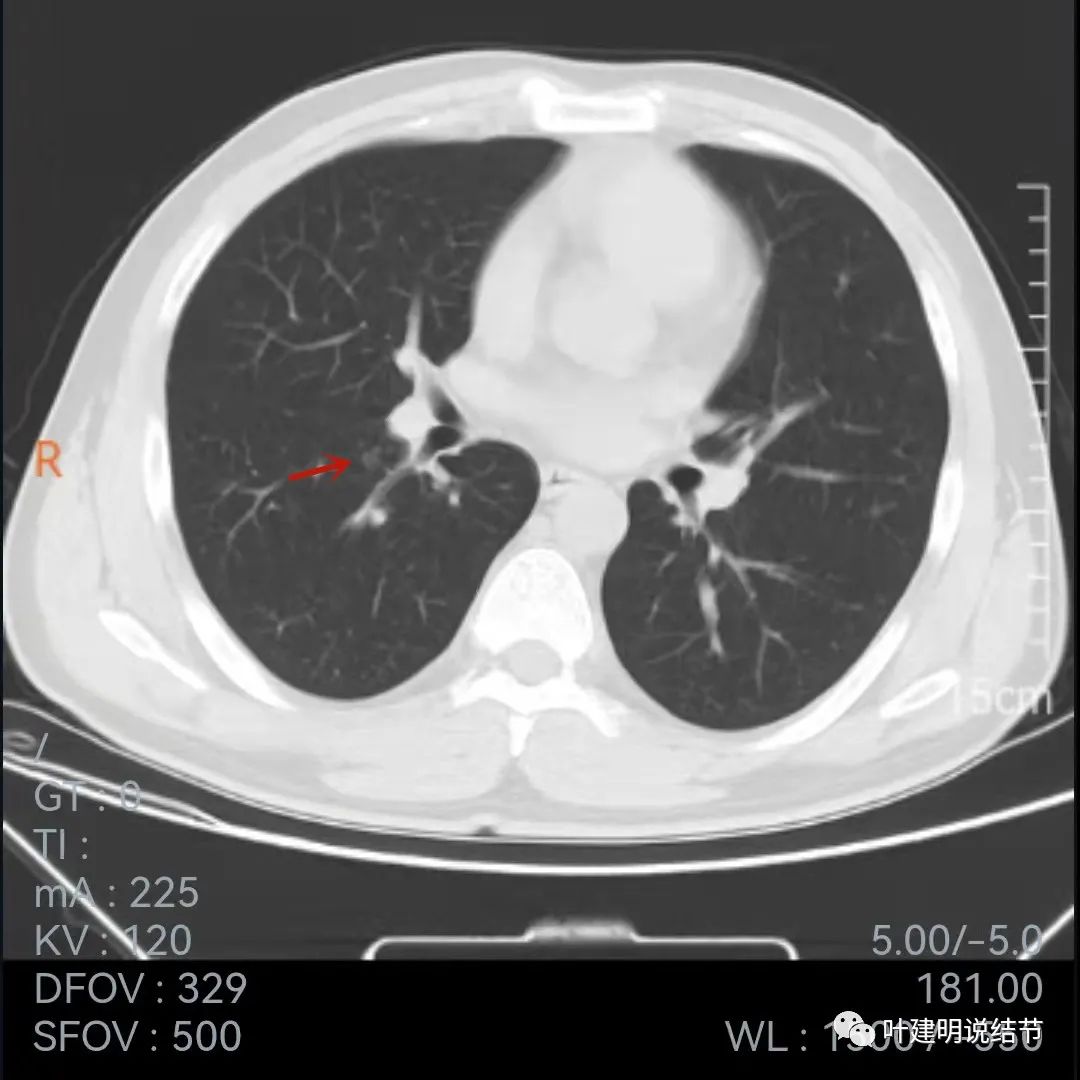

再来看当地医院的靶扫描:

病灶叶间胸膜凹陷,有细毛刺(紫色箭头),但毛刺与病灶大小相比感觉长了点

中间密度还是略低(黄色箭头),胸膜牵拉仍明显(蓝色箭头)

细毛刺(紫色)、胸膜凹陷(蓝色)以及中间偏低密度(黄色)

上图棘突样征象较明显(紫色箭头)

此图不太舒服,胸膜牵拉、表现不平、有微血管征(桔色),但边缘似有少许晕征(绿色),若真是晕征,也是符合肉芽肿性的

上图也示胸膜牵拉、棘突样征,桔色所指似血管进入,但又不太像,增粗的淋巴结管?血管边的是淋巴结吗?不清楚,先不管它

病灶表面不平

病灶密度略不均